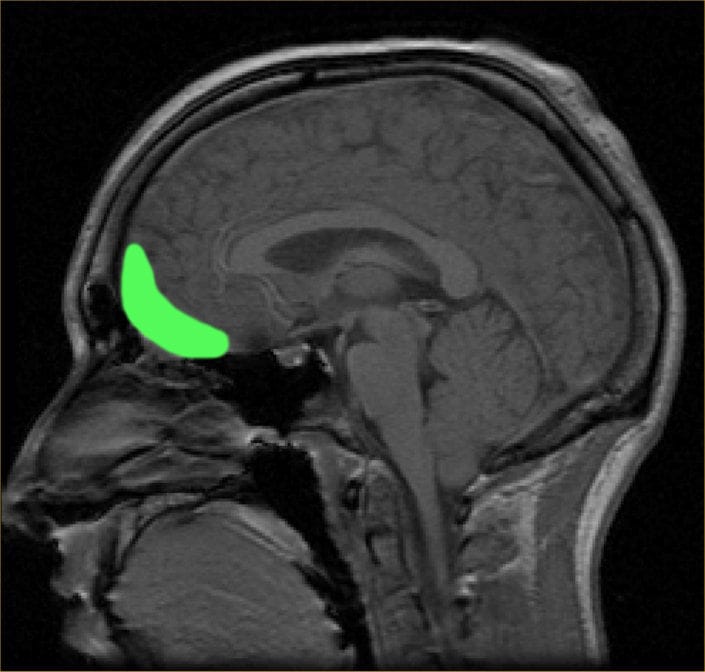

In the case of babies, their big eyes, chubby faces, and small chins trigger an explosion of activity in our orbitofrontal cortex, together with a flush of oxytocin (the hormone that promotes affection) and vasopressin (the hormone that triggers protective urges). The tangled feelings of love and desire to protect and nurture mixing together can be so overwhelming that they short circuit our nervous systems.